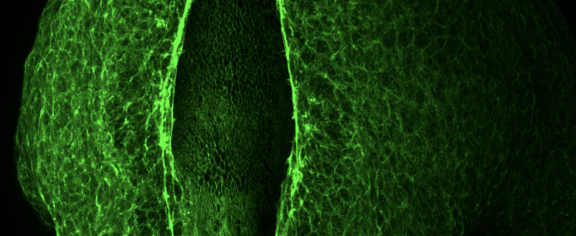

When Postdoctoral Research Fellow Hannah Youngblood’s work on exfoliation glaucoma (XFG) was featured by the BrightFocus Foundation, it caught the attention of Jennifer Rucker, an Alabama resident who was diagnosed with XFG several years ago.